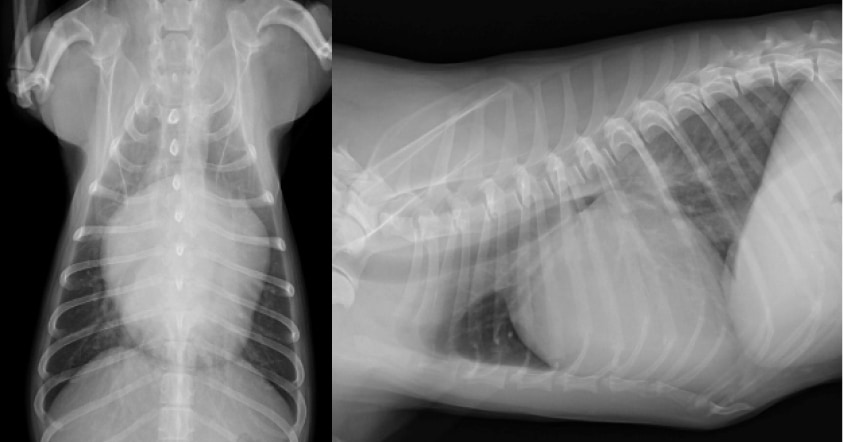

診断は身体検査、超音波検査、レントゲン検査、血圧測定、心電図、血液検査などにより総合的に行います。治療は心臓の負荷を軽減する薬による治療が一般的です。一部施設では手術による治療も行われています。(手術をご希望の方は施設をご紹介いたします)